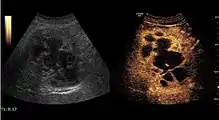

US examination is required to detect liver metastases in patients with oncologic history. In addition, the method can incidentally detect metastases in asymptomatic patients. Early identification (small sizes, small number) is important to establish an optimal course of treatment which can be complex (chemotherapy, radiofrequency ablation, surgical resection) but welcomed. In addition, discrimination of synchronous lesions that have a different nature is also important knowing that up to 25–50% of liver lesions less than 2 cm detected in cancer patients may be benign . US sensitivity for metastases detection varies depending on the examiner's experience and the equipment used and ranges between 40–80% . Sensitivity is conditioned by the size and acoustic impedance of the nodules. For a lesion diameter below 10 mm US accuracy is greatly reduced, reaching approx. 20%. Other elements contributing to lower US performance are: excessive obesity, fatty liver disease, hypomobility of the diaphragm, and certain patterns of hyperechoic or isoechoic metastases that can be overlooked or can mimic benign conditions. Conventional US appearance of metastases is uncharacteristic, consisting of circumscribed lesions, with clear, imprecise or "halo" delineation, with homogeneous or heterogeneous echo pattern. They can be single (often liver metastases from colonic neoplasm) or multiple. Echogenity is variable. When increased, they can compress the bile ducts (which may be dilated) and the liver vessels. Liver involvement can be segmental, lobar or generalized. In this situation a pronounced hepatomegaly occurs. Generally, metastases have non-characteristic Doppler vascular pattern, with few exceptions (carcinoid metastases). Cyst-adenocarcinoma metastases due to semifluid content may have a transonic appearance. When increasing, they can result in central necrosis. CEUS examination is a real breakthrough for detection and characterization of liver metastases.

Increased performance is based on identifying specific vascular patterns during the arterial phase and seeing metastases in contrast to normal liver parenchyma during the sinusoidal phase. CEUS increased accuracy is due to the different behavior of normal liver parenchyma (captures CA in Kuppfer cells) against tumor parenchyma (does not contain Kuppfer cells, therefore CEUS appearance is hypoechoic). To this adds the particularities of intratumoral circulation represented by a reduced arterial bed compared to that of the surrounding normal liver and the absence of the portal vessels . In terms of vascularity, metastases can be hypovascular (in gastric, colonic, pancreatic or ovarian adenocarcinomas) with hypoechoic pattern during arterial phase, and similar during portal venous and late phases, respectively hypervascular (neuroendocrine tumors, malignant melanoma, sarcomas, renal, breast or thyroid tumors) with hyperechoic appearance during arterial phase, with washout during the portal venous phase and hypoechoic pattern 30 seconds after injection.